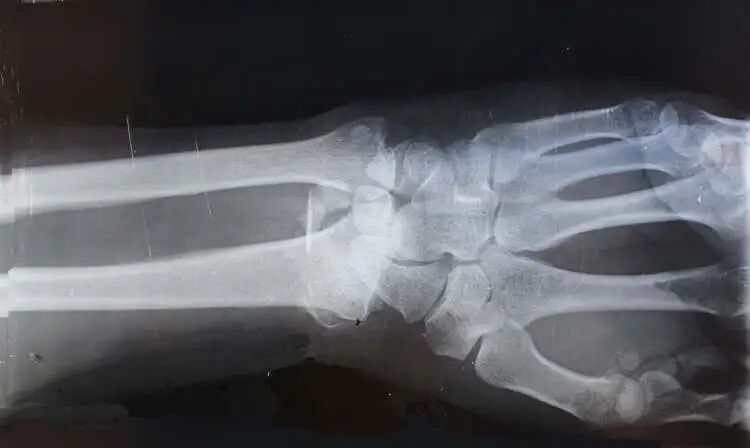

1994年,约翰发生了车祸,现场非常惨烈,足以让一个普通人骨头碎裂的程度。约翰被送到了医院,照了X光,结果医生惊奇地发现,约翰全身上下,找不到一处骨折的地方。

正当大家还在疑惑的时候,医生还发现,约翰的骨密度异常高,是正常人骨密度的8倍。

骨密度,是指单位体积的骨头里骨矿物质的质量,是判断骨骼是否健康的一个指标,一个成年男性骨密度值大约为1.228g/cm3,骨密度的8倍,可想而知,这个人的骨头是多么地致密和坚硬了。